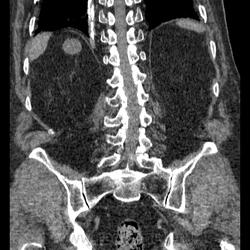

КТ ОБП+С Объемное гиперваскулярное образование почки. Почечно-клеточный рак.

Мужчина 82 года. Отец коллеги с другого отделения. На УЗИ киста почки. Решили сделать КТ. Жалобы на боль в поясничном отделе позвоночника (неудивительно из-за жуткого остеохондроза и м/п грыж). Макрогематурию отрицает. Микрогематурии не выявлено по ОАМ, лишь протеинурия. Кисты подтвердились ну и черт с ними  хуже то, что в верхнем сегменте правой почки похоже ПКР, характеристика контрастирования соответсвует, тем более еще свеж в памяти предыдущий случай. Смущают надпочечники, не "стрельнул" ли в правый mts? А в опухоли гиподенсивный учаток в артериальную фазу - участок некроза, кровоизлияния?

Почечно-клеточный рак, гистологически - светлоклеточный, степень дифференцировки не помню.

Образование в верхнем полюсе правой почки: гиперденсивное в артериальную фазу, гиподенсовное в венозную и отроченную = почечно-клеточный рак